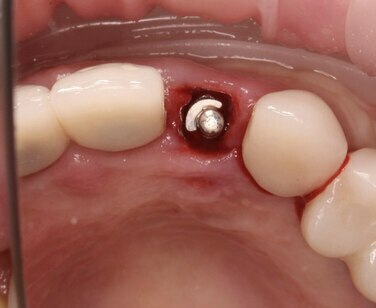

Одномоментная имплантация и немедленная нагрузка

Винтовая фиксация, одномоментное формирование профиля прорезывания.

Дистальный разрез для снятия напряжения с мягких тканей.

Немедленная нагрузка и мягкотканная пластика